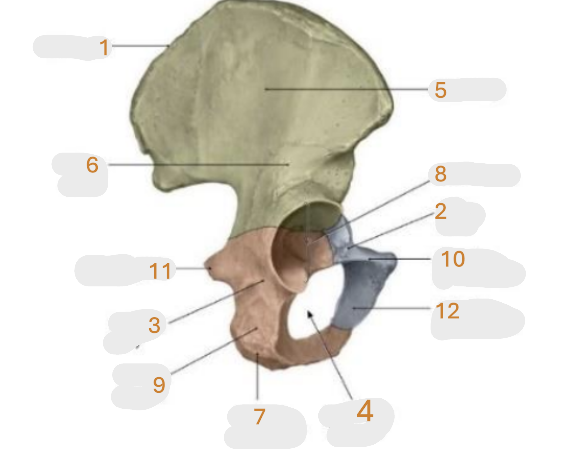

Where is the iliac crest

1

where is the sacral canal

2

Where is the iliac tubercle

3

Where is the outer lip

4

Where is the inner lip

5

Where is the iliac fossa

6

Where is the pectineal line (pecten pubis)

7

Where is the sacroiliac joint

8

Where is the ischial spine

9

Where is the iliac tuberosity

10

Where is the promontory

11

Where is the arcuate line

12

Where is the anterior superior and inferior iliac spine

13

Where is the intermediate line

14

Where is the ala of the sacrum

15

Where is the coccyx

16

Where is the pubic crest

17

Where is the pubic tubercle

18